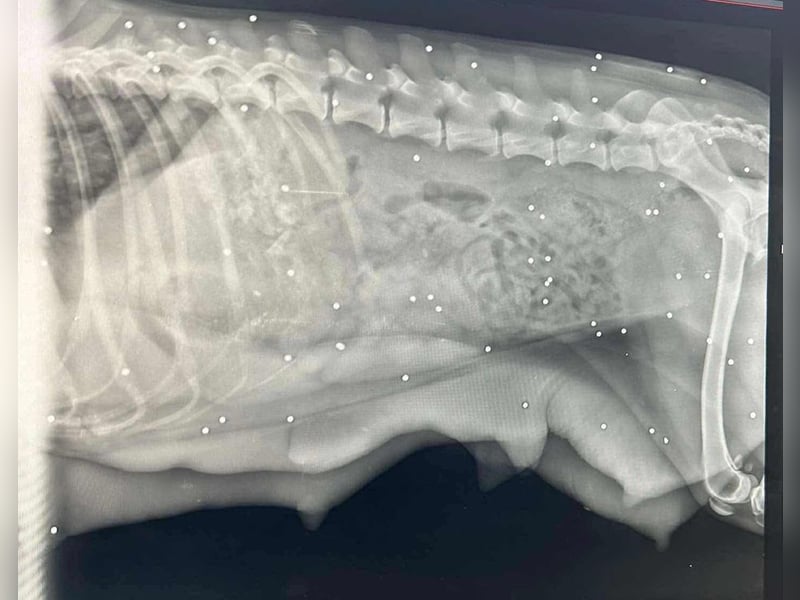

Bemerkungen: Auf die Hündin wurde wohl geschossen. Sie ist geröngt, allerdings steht das medizinische Gutachten noch aus.